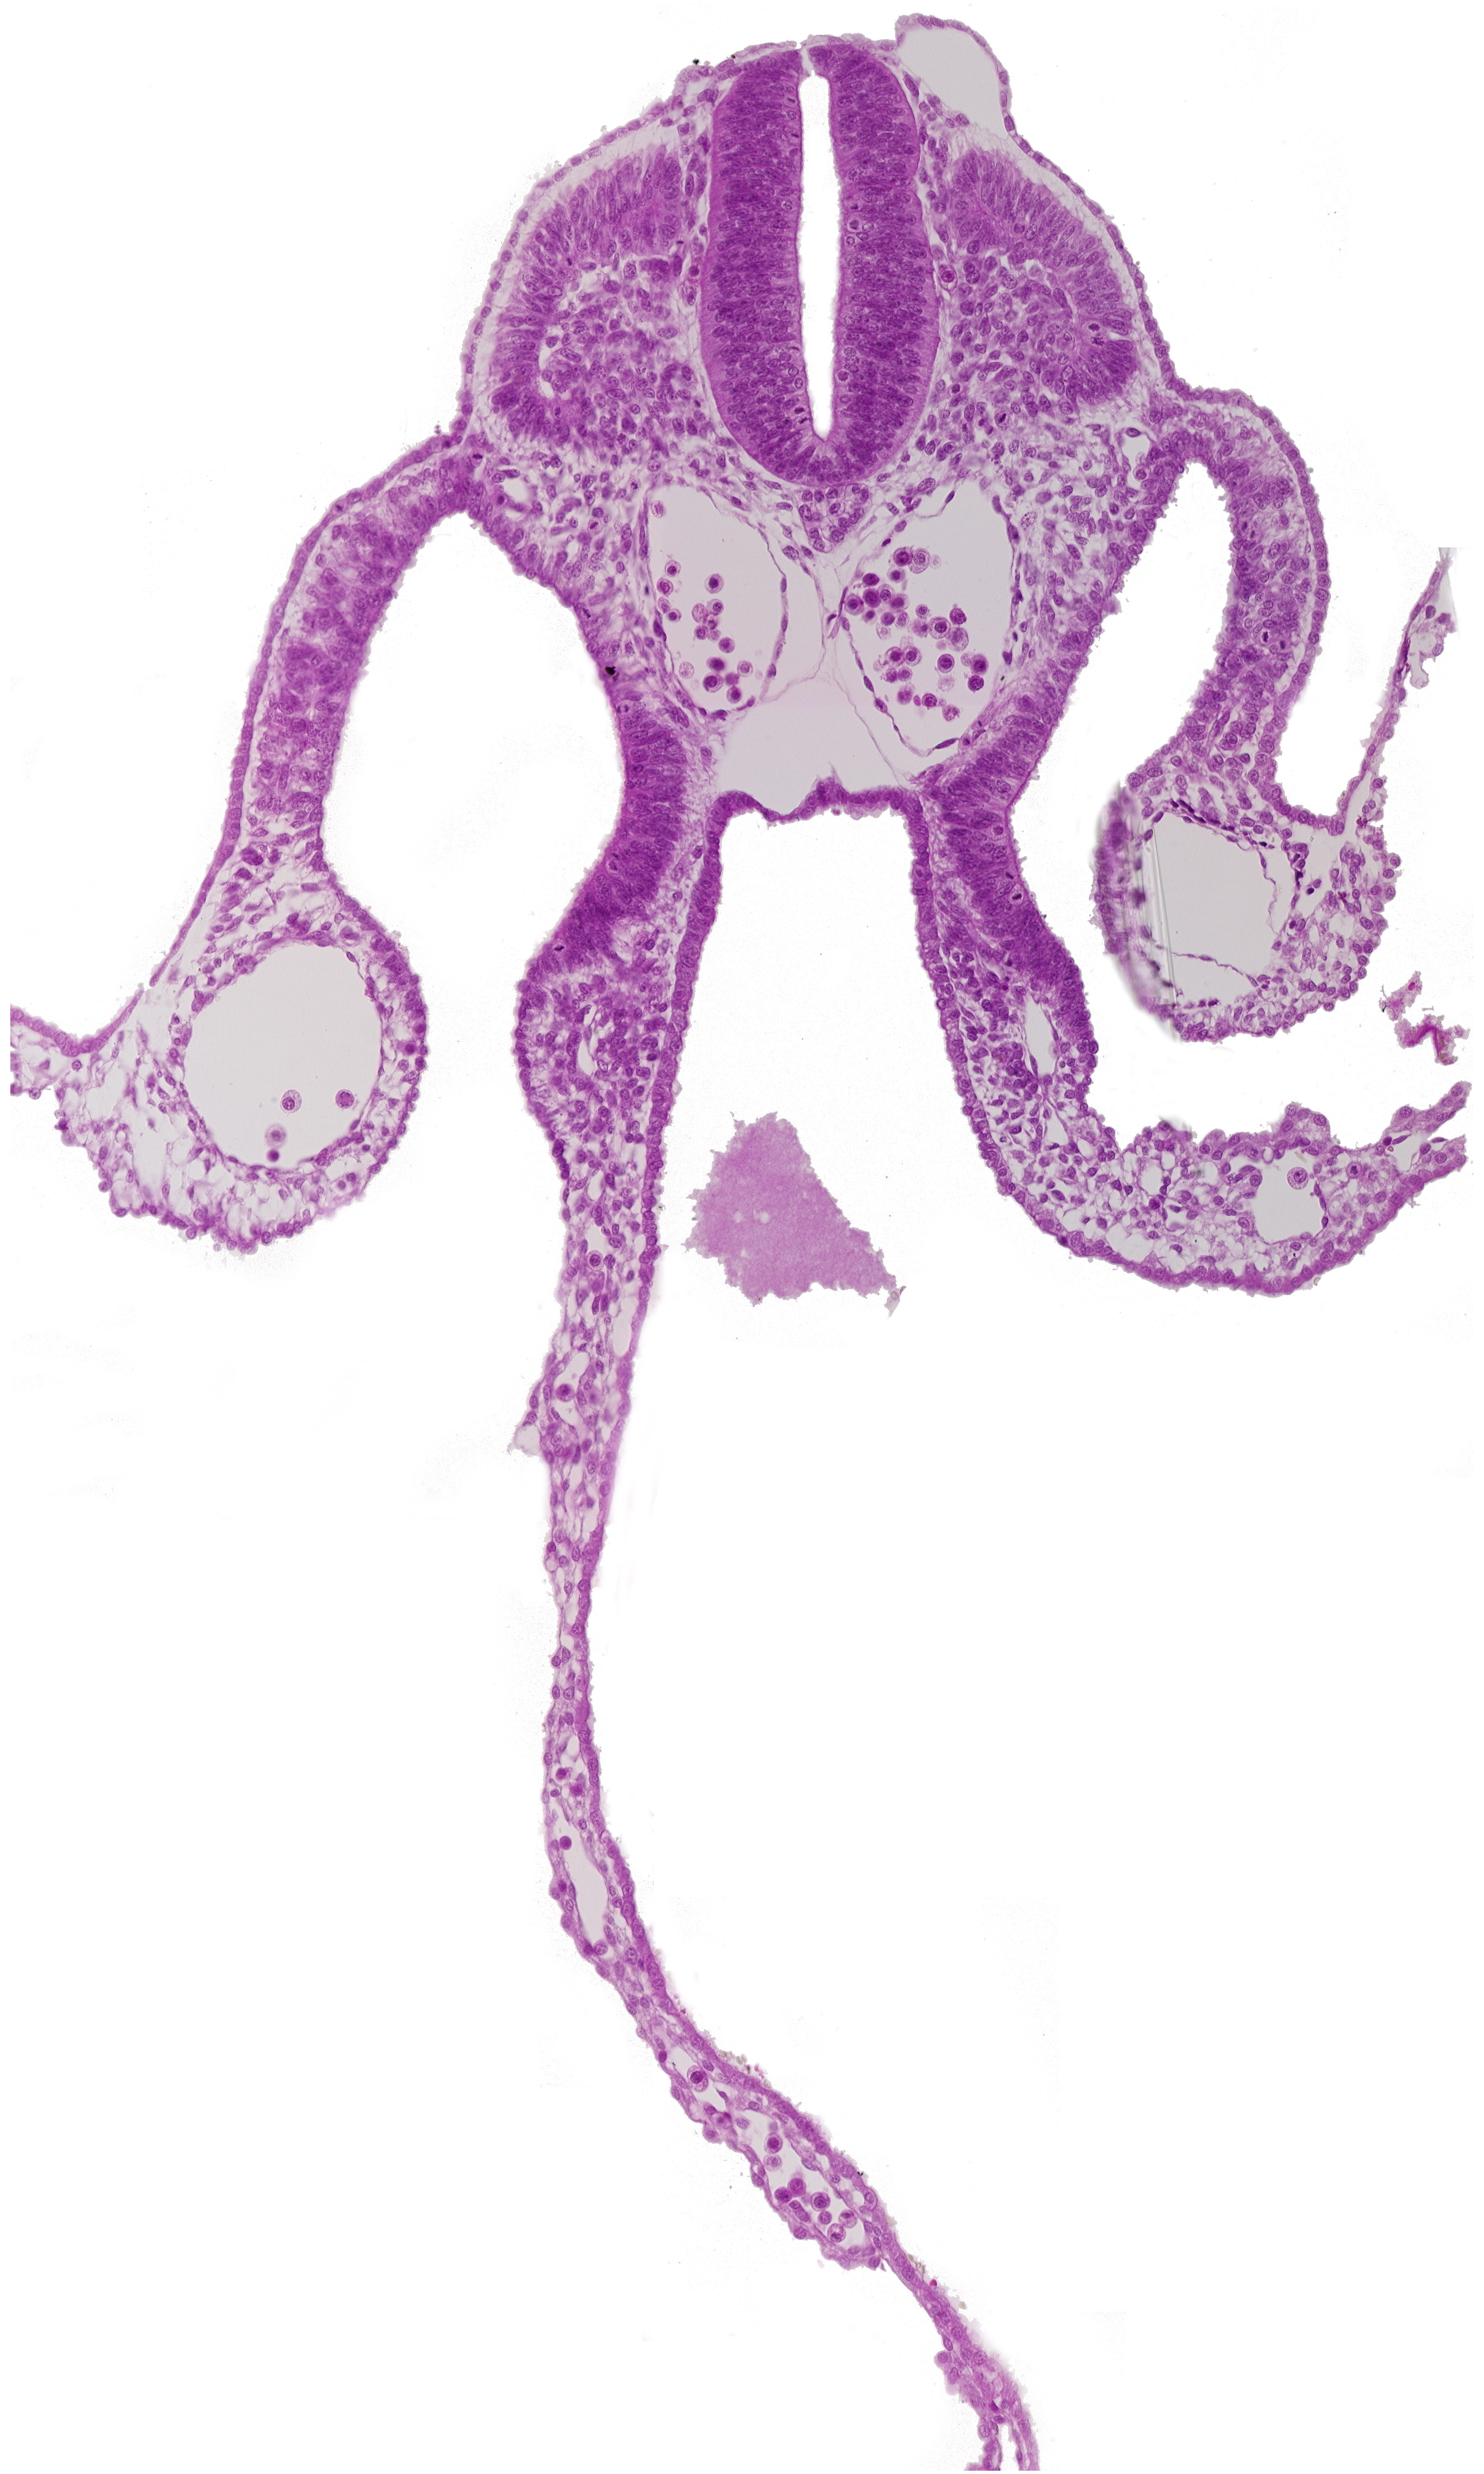

Carnegie Embryo #8943   |   Location: 06-02-02

Keywords: amniotic cavity, dermatomyotome 8 (C-4), dorsal aorta, dorsal intersegmental artery, endoderm, extra-embryonic coelom, notochord, peritoneal cavity, sclerotome, somatopleuric mesoderm, splanchnopleuric mesoderm, umbilical vesicle cavity